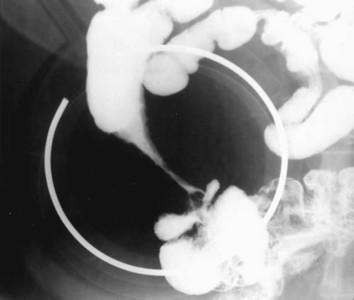

A 32 year old woman presents to her physician with a history of chronic diarrhea. A colonscopy reveals chronic inflammation in different portions of her bowel, including her terminal ileum. Based on the gross specimen below, what is the differential diagnosis? Based on her symptoms, what is her likely diagnosis?

Strictures caused by: chronic ischemia, cancer or Crohn disease

Crohn stricture: transmural strictures, fissures, creeping fat, abscesses; seen in terminal ileum, skip lesions, rectum spared, can affect ANY part of columnar GI tract

Crohn disease: string sign

* Yersinia infection can mimic Crohn Disease